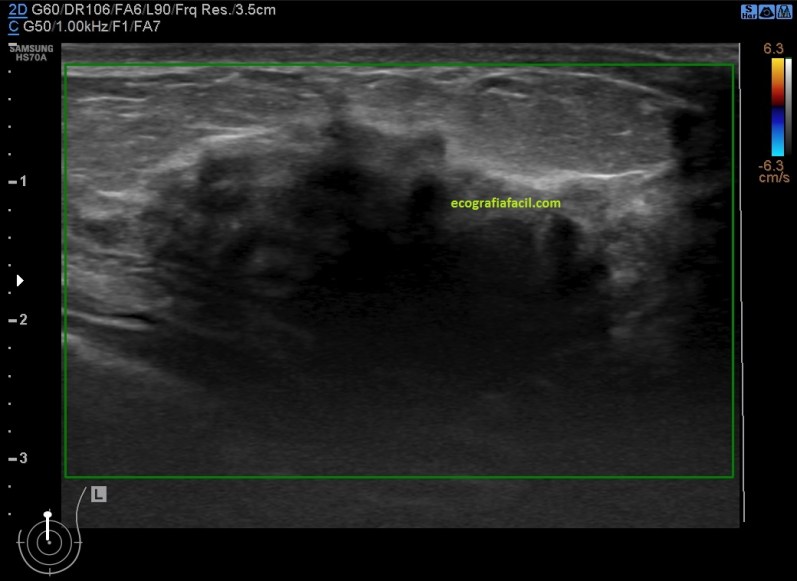

El estudio ecográfico mostró:

1. Mamas de predominio fibroso.

2. Acúmulos de tejido asímétricos de tejido fibroso de aspecto altamente denso e hipoecogénico de contorno mal definido en ambas mamas con ausencia de doppler color.

Imágenes:

3. Mastopatía Diabética

De la imagen 3 a la 6 tienes el aspecto semiolólogico normal de una mama diagnosticada de Mastopatía Diabética.